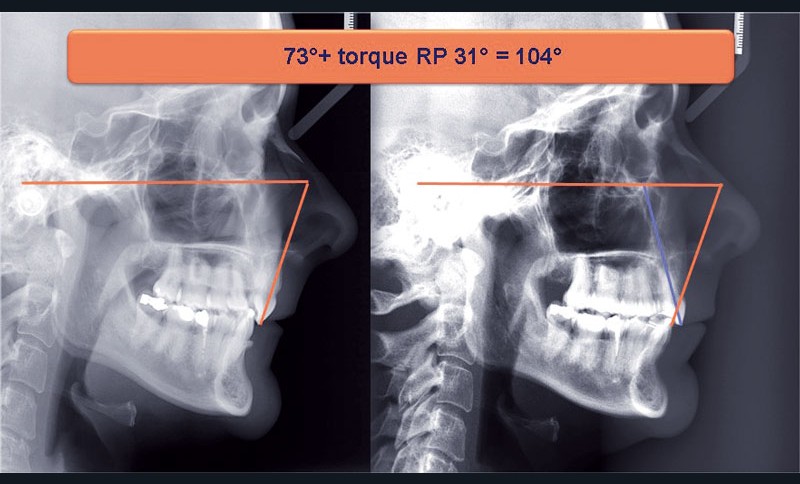

Nous lui avons donc proposé un traitement d’alignement avec maintien des 14 et 24 en position de 13 et 23 et optimisation du torque pour favoriser un développement des arcades et chercher à améliorer le sourire et le soutien labial.

Un appareillage Damon métal a été mis en place, réalisé à partir d’un set up numérique Insignia pour obtenir un contrôle précis des torques et de la forme d’arcade et réduire le temps de finition grâce à un collage indirect très précis.

Les objectifs de traitement ont été remplis. Nous avons observé un excellent contrôle du torque et une absence de perte de l’occlusion postérieure grâce à la technique Insignia.